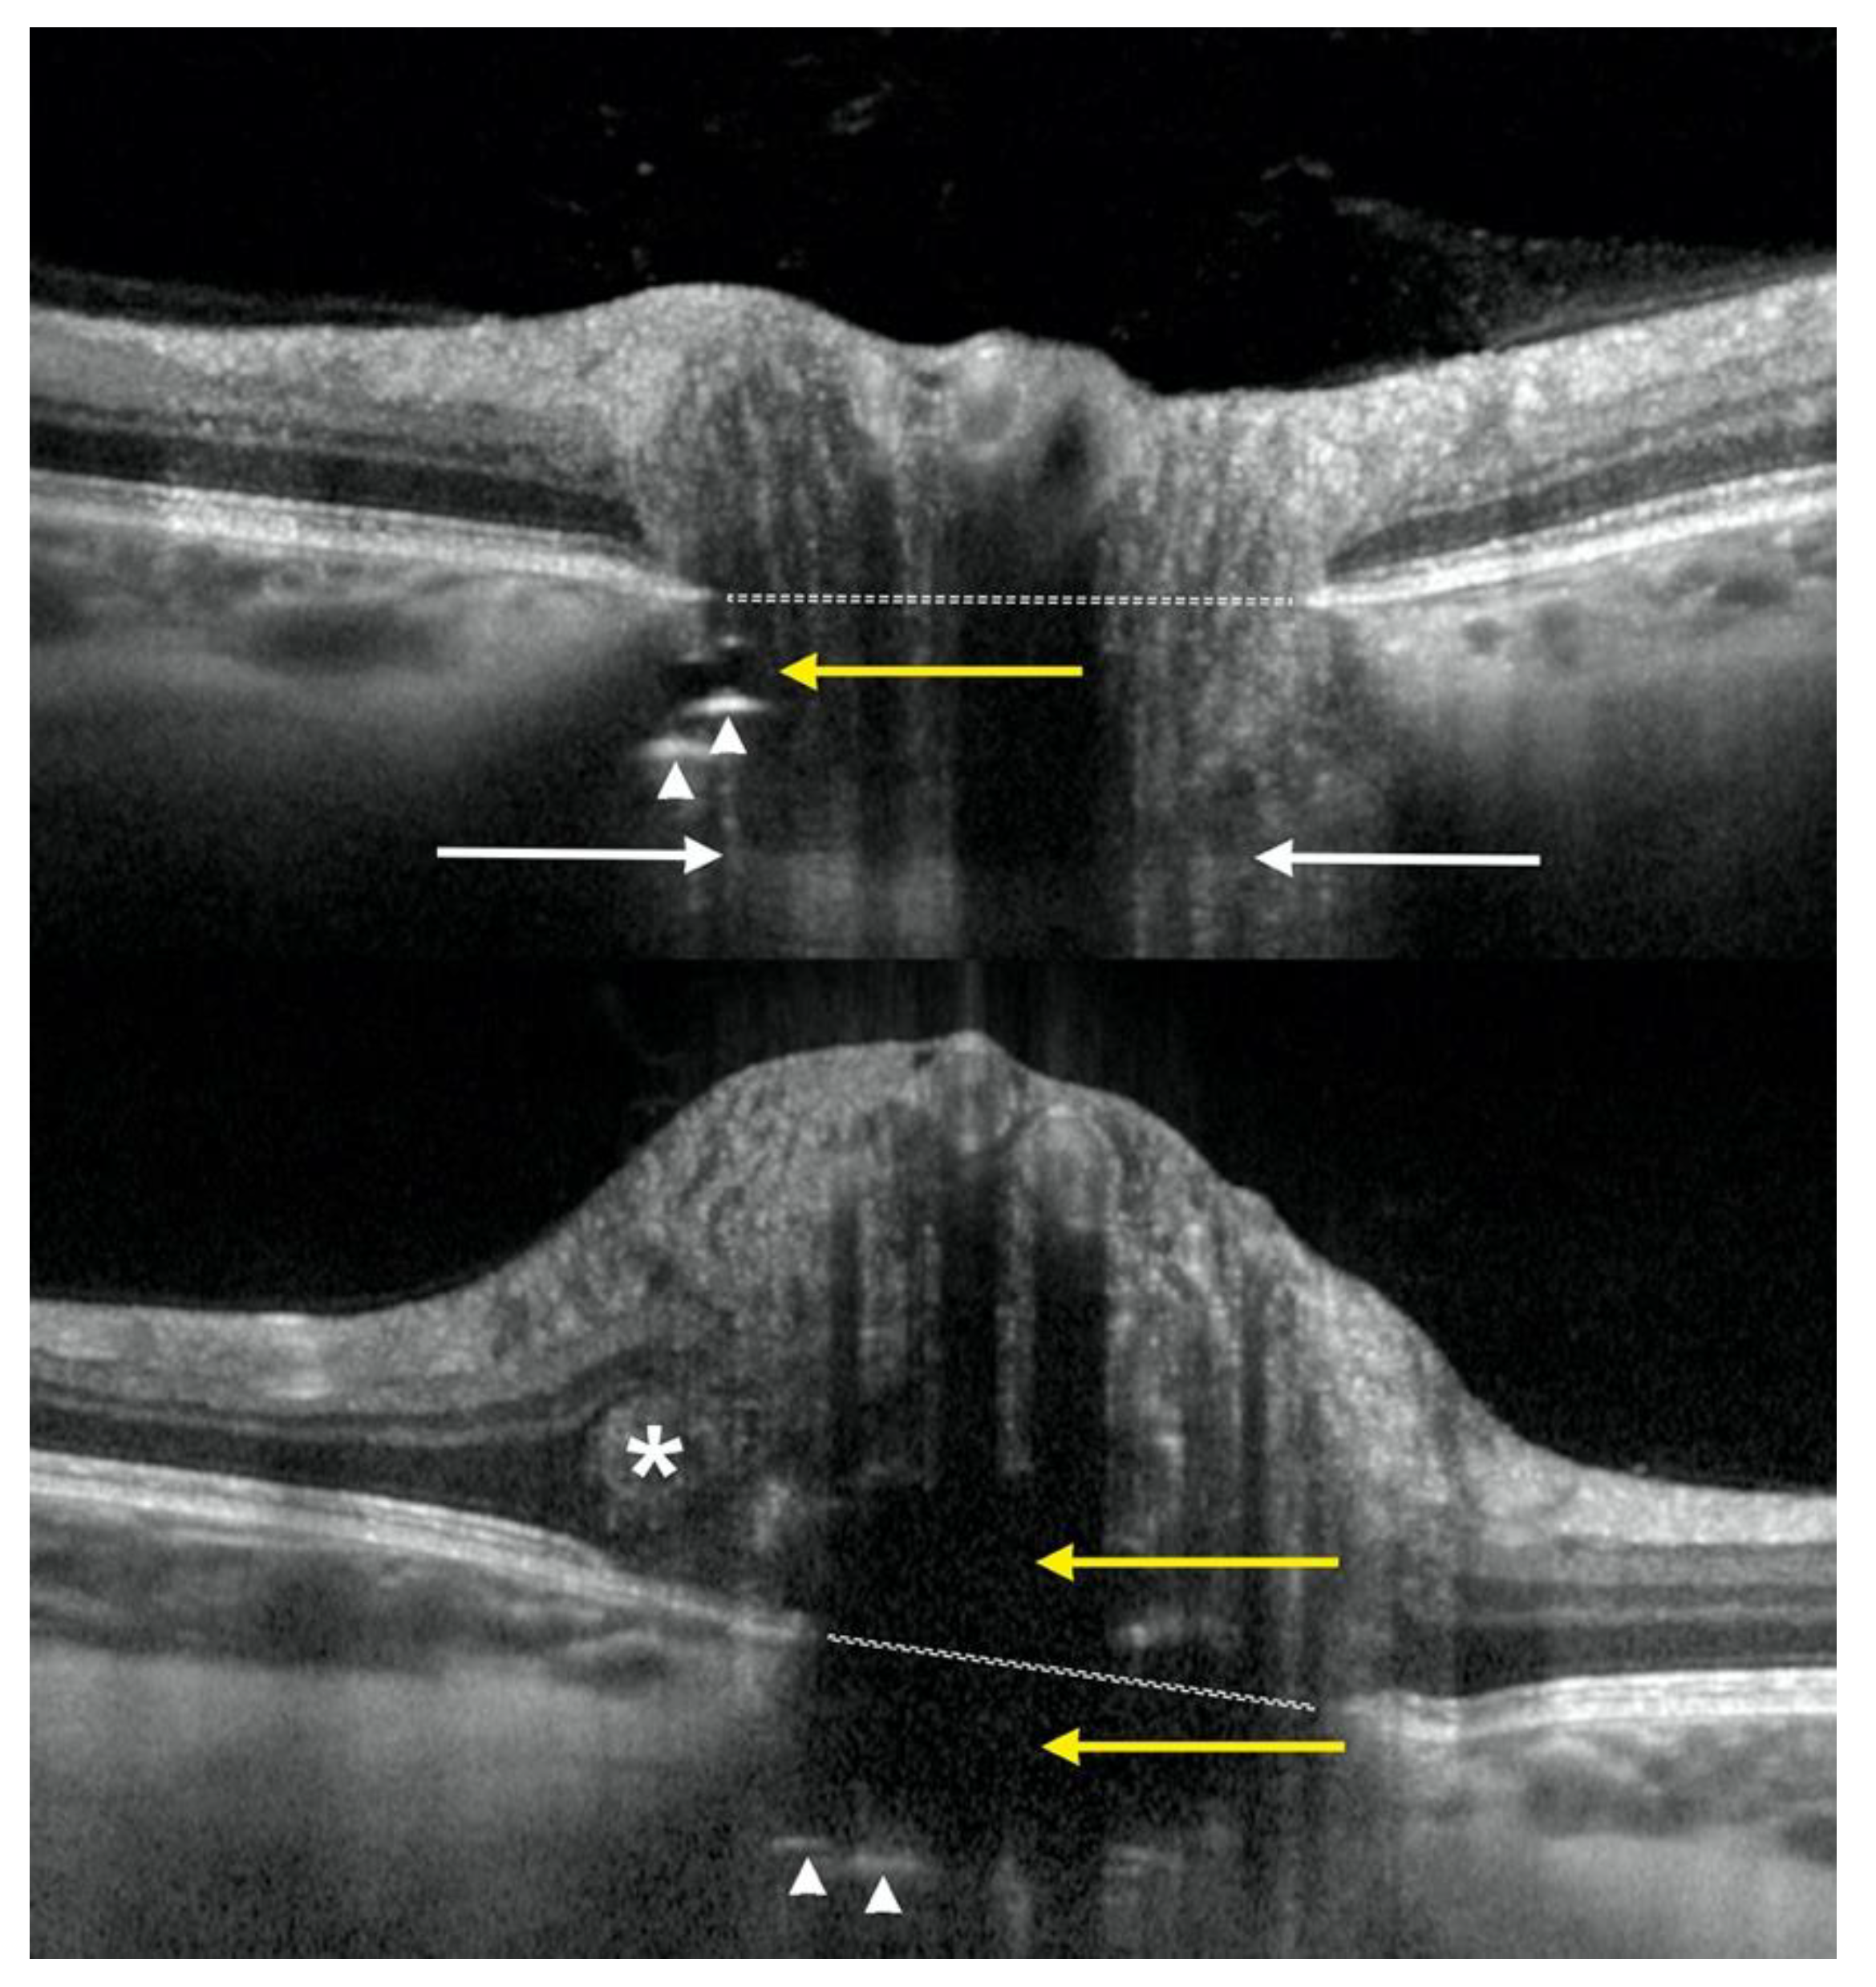

We performed a retrospective comparative study of SD-OCT and SS-OCT imaging modalities for detecting ODD and associated changes located deep in the ONH. Included in this study were patients who had undergone SD-OCT EDI imaging performed according to the Optic Disc Drusen Studies Consortium recommendations [12], as well as a high-resolution SS-OCT angiography scan of the ONH as part of standard clinical care. Other inclusion criteria were the presence of at least one ODD or a part of one ODD below the level of BMO, i.e., a deep ODD, (Figure 1), and/or the presence of prelaminar HLs below the level of BMO. Furthermore, the presence of additional superficial ODD, i.e., ODD located above the level of BMO, were allowed if the changes were not extensive enough to visibly obstruct the imaging of deeper ONH structures. Exclusion criteria were an image quality score lower than 20 and 40 for SD-OCT and SS-OCT, respectively, or scan properties that differ from the settings mentioned subsequently. Patients were imaged between November 2018 and November 2020 at the Department of Ophthalmology, Rigshospitalet, Glostrup, Denmark, when they visited the neuro-ophthalmology clinics for ODD workups. We adhered to the Declaration of Helsinki in conducting this study.

Figure 1. Enhanced depth imaging OCT showing two cases of deep optic disc drusen with associated features and landmarks: level of Bruch’s membrane opening (dotted white line) and visible level of lamina cribrosa (white arrows), optic disc drusen as signal-poor, hyporeflective irregular shaped areas (yellow arrows) with slightly hyperreflective margins, prelaminar hyperreflective lines (white arrow heads), and PHOMS (asterisk).